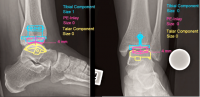

Mô-đun "Foot" tạo điều kiện cho việc lập kế hoạch tối ưu, cũng như như xác định kích thước và vị trí của dụng cụ kết hợp xương cho bàn chân, mắt cá chân và ngón chân.